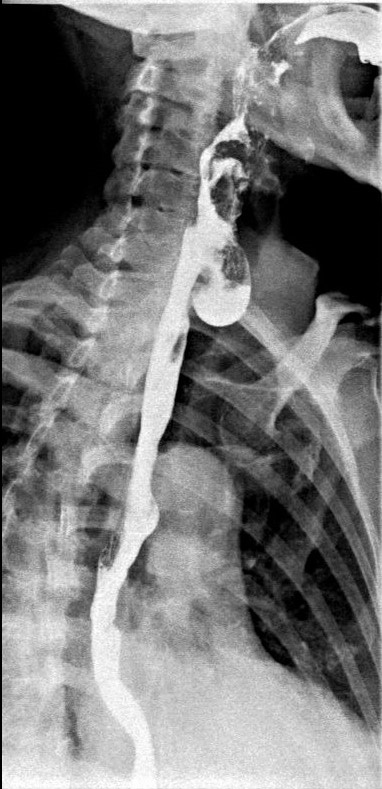

A la paciente se le realizó también un estudio esófago-gastroduodenal (EGD) para su diagnóstico. Se obtuvieron imágenes del esófago mientras que la paciente bebía contraste baritado, observándose el divertículo esofágico (KJ). Comenzamos el estudio en bipedestación (imágenes 6 y 7), después tomaremos imágenes en prono, imagen 8.

Imágenes en OPI en bipedestación donde se observa el paso de contraste por el esófago y una imagen sacular: divertículo esofágico

Imagen 8 en OAD en prono donde se observa el paso de contraste por el esófago.